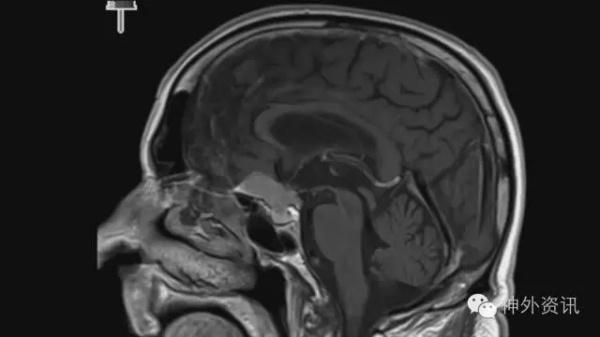

图11、12是一例常见的基底位于鞍结节鞍隔脑膜瘤。手术常规右侧LSO入路,先断肿瘤基底,然后分水离肿瘤界面,予以切除。

图11. 鞍结节鞍隔脑膜瘤。

图12. 鞍结节鞍隔脑膜瘤

图13. 术中探查右侧第二间隙。

图14. 右侧颈内动脉撕裂,动脉血满视野。

术中在探查右侧第二间隙时,较尖的双极头端不慎将颈内动脉撕破,动脉血汹涌(图13、图14);此种情况下,压迫止血肯定不靠谱,予以9-0缝合亦不现实,因此Sundt Clip Graft可能是唯一救命方案。选用5mm内径的Sundt Clip Graft,上夹固定后,止血彻底;术中超声探查血流通畅;继续切除肿瘤完成手术,术后复查良好。

图15. Sundt Clip Graft包裹颈内动脉破口。

图16. 术后复查见脑组织无肿胀缺血。